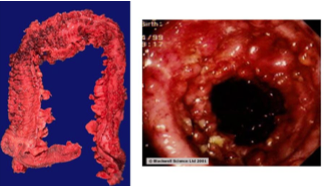

35 year old male presents with colicky abdominal pain and diarrhea 4-5 times a day for the past 2 years. What is his differential and diagnosis based on the colonoscopy image below?

Celiac sprue:

- Antibodies to gliadin

- Distal duodenum, proximal jejunem

- Loss of villi on histology

Malabsorption of:

- Vitamin K–> hemorrhagic diathesis

- Iron deficiency

- associated with dermatitis herpetiformis

- Increased risk of malignancy (T-cell lymphoma)

Labs:

Colonoscopy= celiac sprue; see small-bowel scalloping

Testing:

- Gluten-containing diet before biopsy, response to gluten-free diet

- Serology: Anti-tTG IgA (anti-tissue transglutaminase; high sensitivity, specificity), serum IgA (to rule out IgA deficiency= false negative), anti-endomysial, HLA testing of DQ2/DQ8

- Thyroid function tests

- Stool (WBCs, ova, parasites, culture)

- Colonoscopy for: colonic polyps, IBD, collagenous colitis, microscopic colitis

- Be careful with biopsies from duodenal bulb: subjected to physiologic peptic injury–> broader, shorter villi and increased PMNs in normal physiologic state